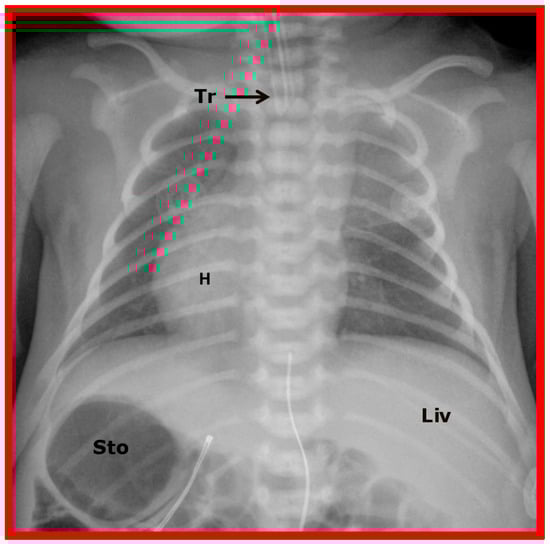

Figure 8. A chest roentgenogram of an infant demonstrating that the heart (H) is located in the right chest (dextrocardia), and there is left to right reversal of viscera (situs inversus). In this condition, the liver (Liv) is on the left side of the abdomen while the stomach (Sto) is on the right, i.e., situs inversus totalis. Tr, trachea. Reproduced from reference [4].

This term situs inversus totalis signifies the inversion of both heart and viscera, i.e., dextrocardia and situs inversus together (Figure 2B and Figure 8)

Isolated dextrocardia is a phrase used to characterize subjects with dextrocardia, but the viscera are normal in position (situs solitus), i.e., dextrocardia with situs solitus (Figure 3 and Figure 10).

Figure 10. A chest roentgenogram of a baby illustrating dextrocardia along with normal visceral position (situs solitus) with the liver (Liv) on the right side and the stomach (Sto) on the left side, i.e., isolated dextrocardia. The tracheal (Tr) position in the middle is shown. The Sto is dilated, probably related to intestinal obstruction secondary to malrotation of the gut. Modified from reference [4].